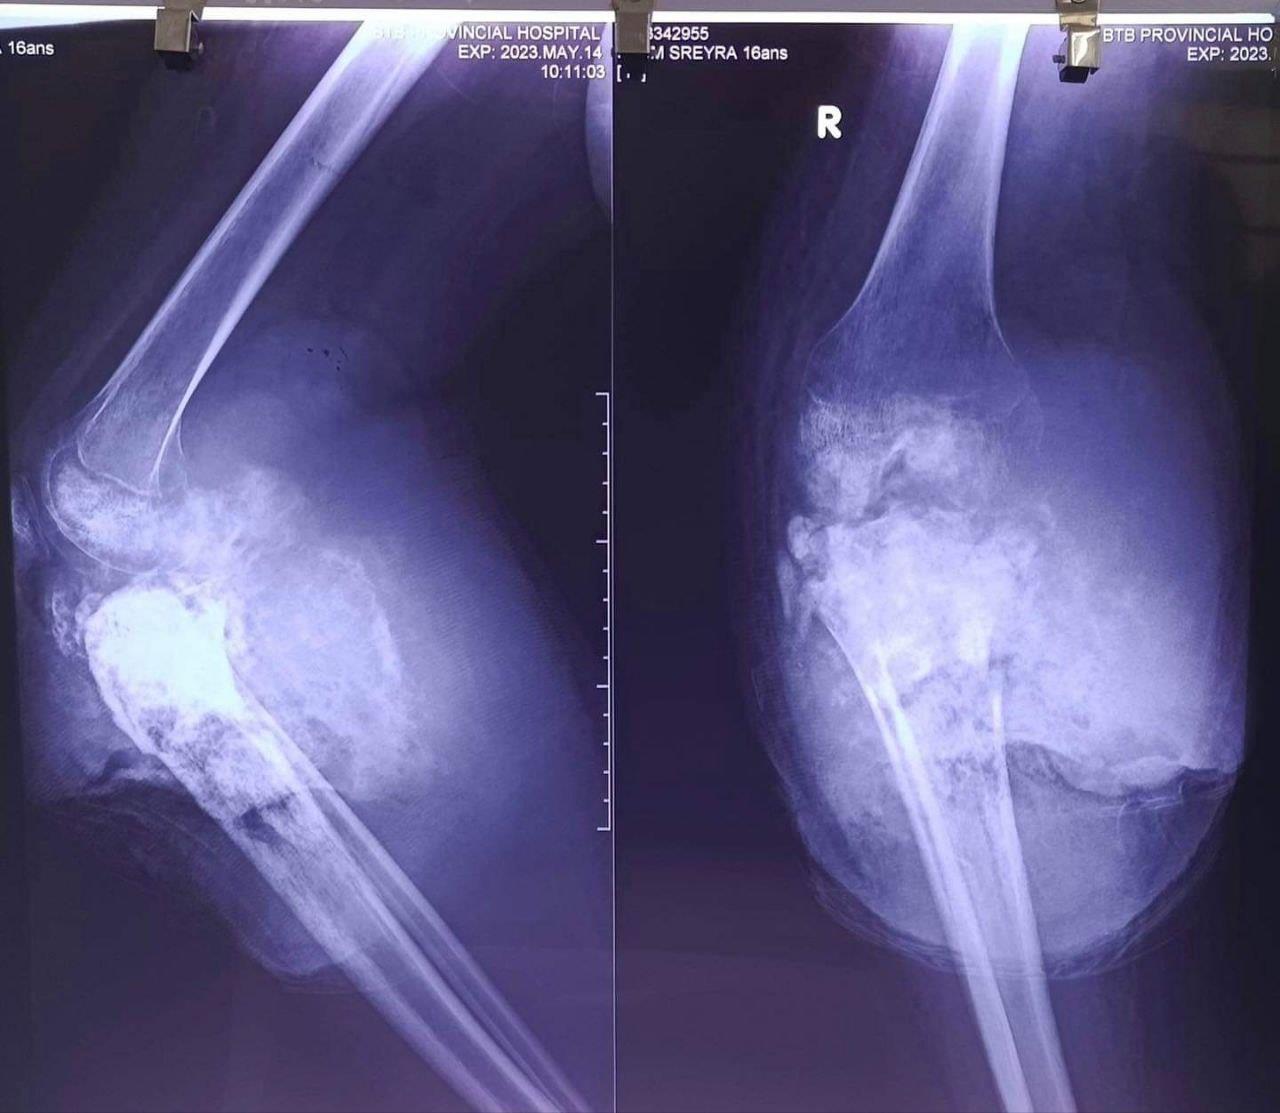

ក្រោយទទួលបានព័ត៌មានថាប្អូនស្រីសៀប ស្រីរ៉ា អាយុ១៦ឆ្នាំ ជាសិស្សវិទ្យាល័យបួ រស់នៅភូមិអន្លង់ស្តី ឃុំបួរ ស្រុកភ្នំព្រឹក ខេត្តបាត់ដំបង មានជំងឺមហារីកជើងធ្ងន់ធ្ងរ នៅថ្ងៃទី១៤ ខែឧសភា ឆ្នាំ២០២៣នេះ លោក សុខ លូ អភិបាលខេត្ត និងជាប្រធានគណៈកម្មាធិការសាខាកាកបាទក្រហមកម្ពុជាខេត្តបាត់ដំបង និងភរិយា បានចាត់ឲ្យក្រុមគ្រួសារពេទ្យមណ្ឌលសុខភាពបួ ស្រុកភ្នំព្រឹក បញ្ជូនមកព្យាបាល និងធ្វើការវះកាត់នៅមន្ទីរពេទ្យខេត្តបាត់ដំបង។

ពេលនេះដែរប្អូនស្រី និងក្រុមគ្រួសារបានមកដល់មន្ទីរពេទ្យ ដោយមានការយកចិត្តទុកពីសំណាក់ក្រុមគ្រូពេទ្យ និងត្រូវបានពិនិត្យតាមដែនដោយយកចិត្តទុកបំផុត។ ដោយស្ថានភាពជំងឺមហារីកជើងធ្ងន់ធ្ងរ និងដោយមានការ យល់ព្រមពីគ្រួសារ ប្អូនស្រីត្រូវបានបញ្ជូនចូលបន្ទប់វះកាត់ ដោយតម្រូវធ្វើការវះកាត់បន្ទាន់៕ ផ្តល់សិទ្ធិដោយ៖ freshnews